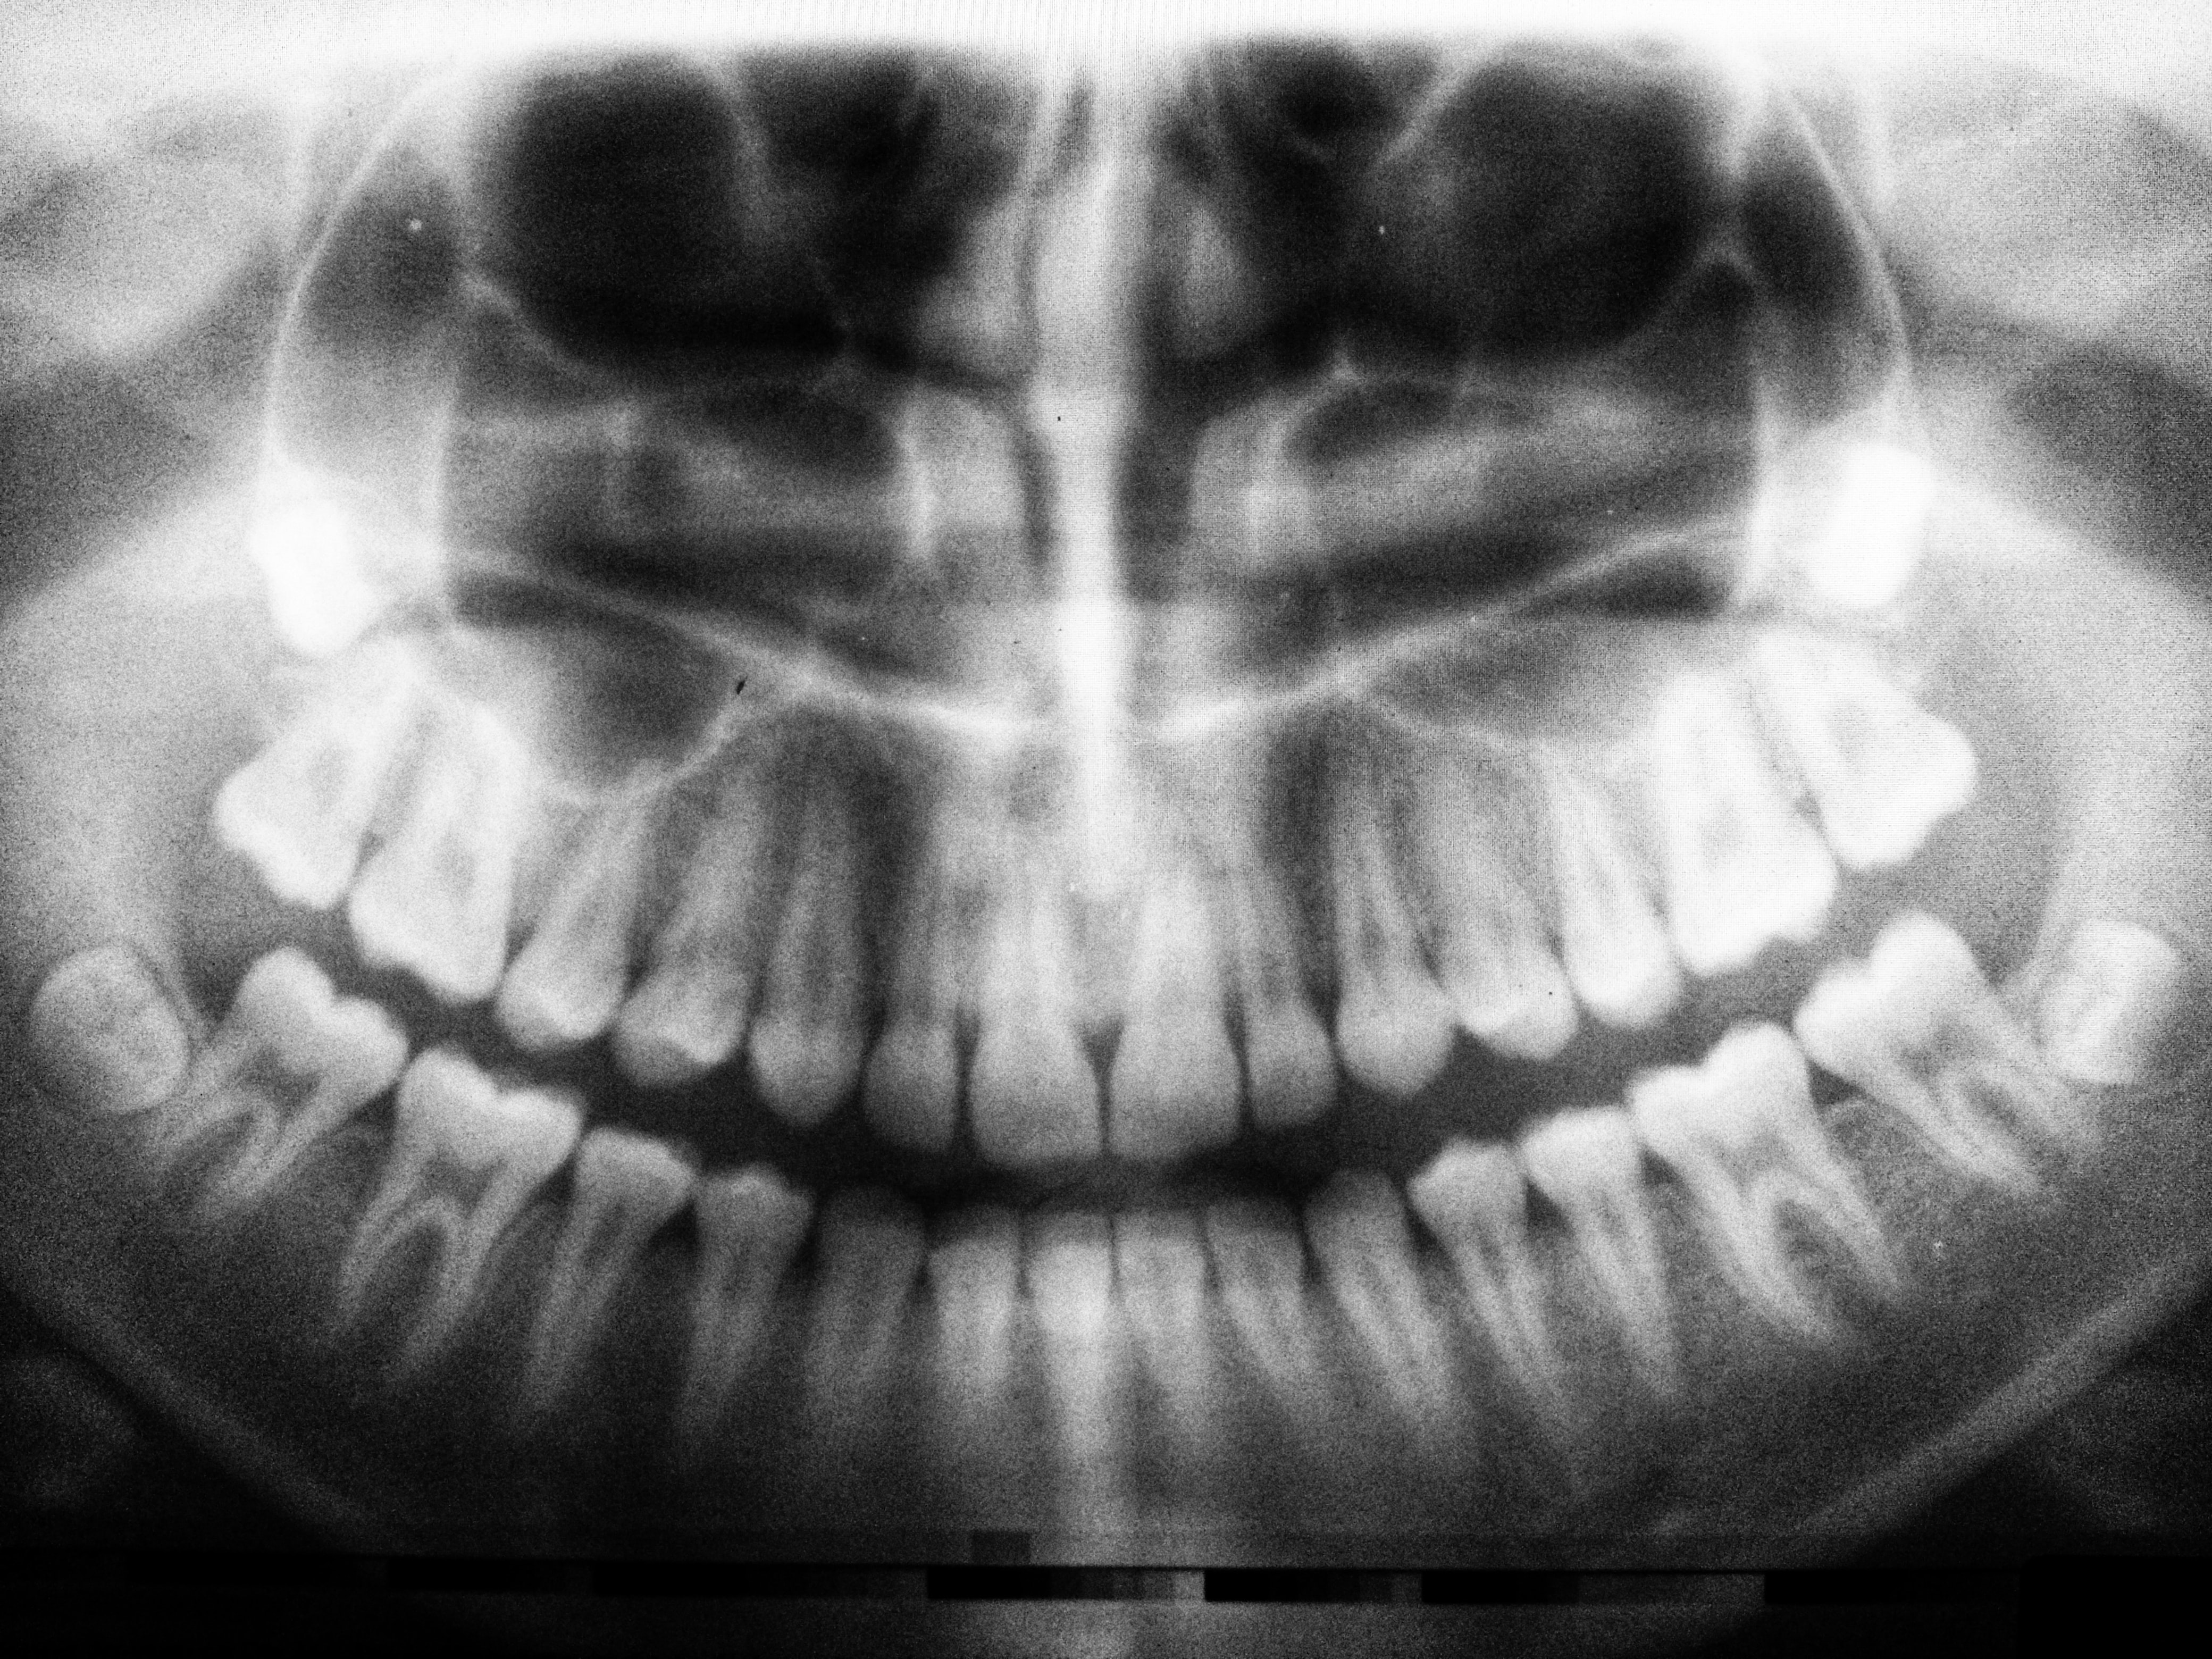

임플란트란?

상실된 치아를 인공 치아의 이식을 통해 건강한 구강을 가지게 하는 의학의 한 분야입니다. 본래는 인체의 조직이 상실되었을 때 이를 회복시켜 주는 대치물을 의미하지만 치과에서는 인공 치아 이식을 말합니다.